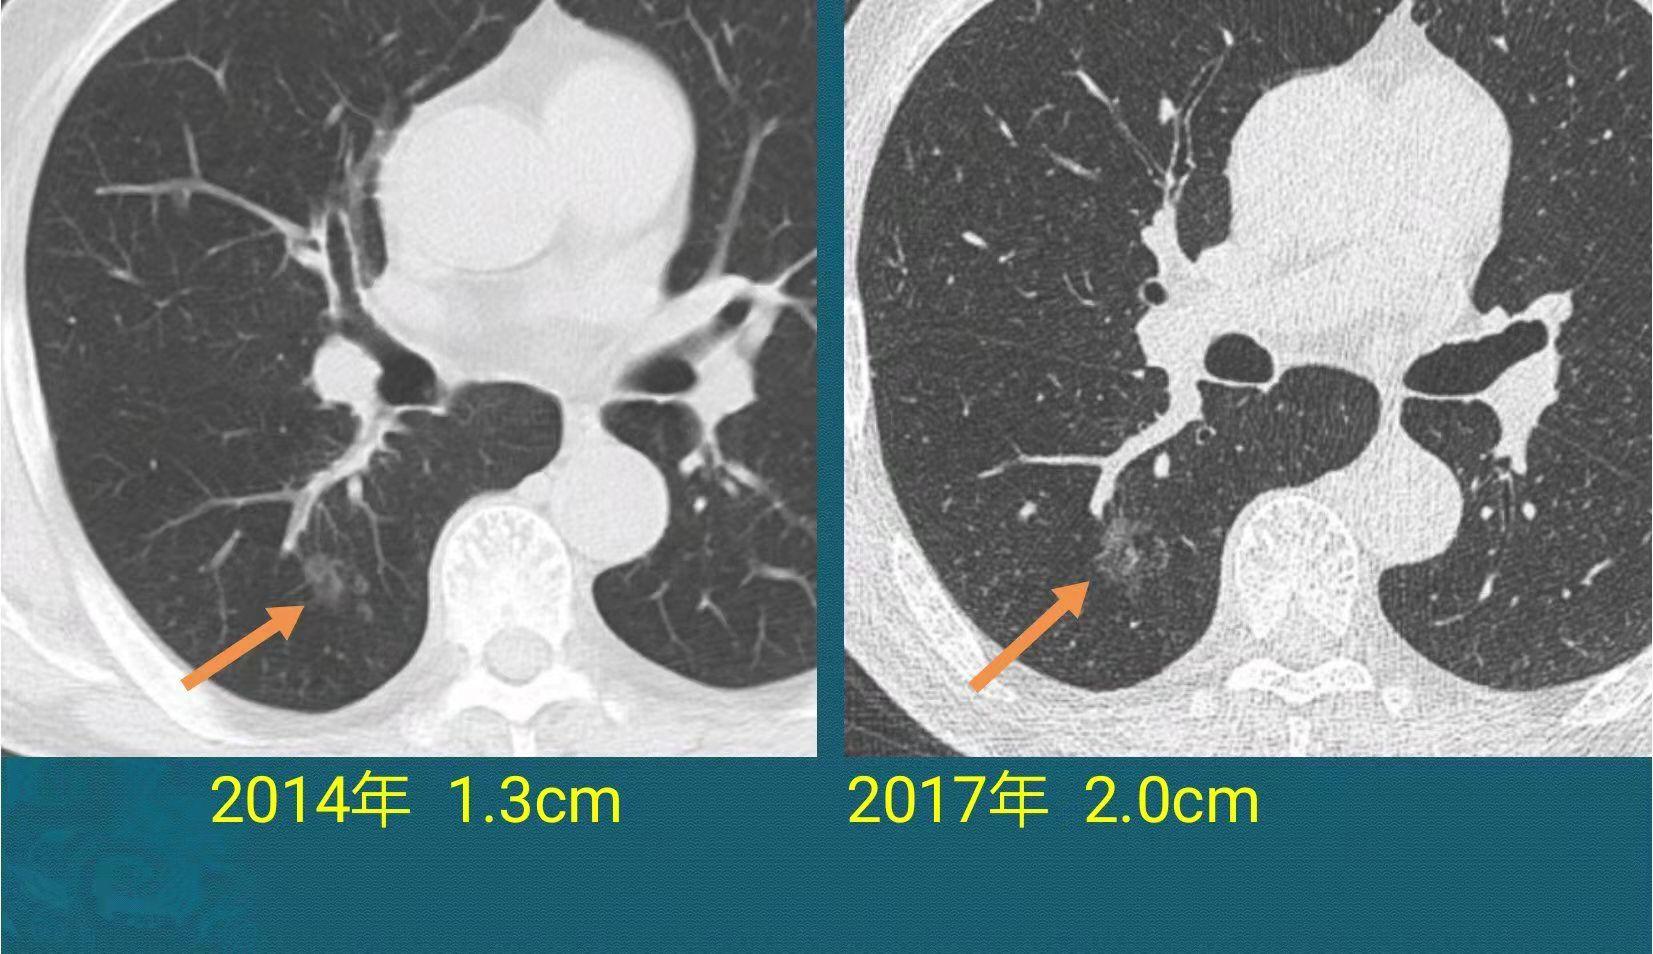

第三例,中年女性,无症状,体检发现磨玻璃肺结节:

结节位于右下肺,一开始密度很淡,长径1.3cm,旁边还有两个微小结节。

纯磨玻璃结节大多数是惰性病灶,可以定期复查,发现进展再手术也来得及,因为纯磨玻璃结节不转移。

她倒也心大,一晃隔了3年才复查(没有症状,也就没过多在意),结果到2017年的时候结节增到到2.0cm,3年长了7毫米,原来那个较大结节跟边上两个微结节融合到一起了。

这个时候就有必要手术了,病理是肺腺癌,贴壁生长为主,没有低分化成分,没有淋巴结转移,现在4年了没复发。